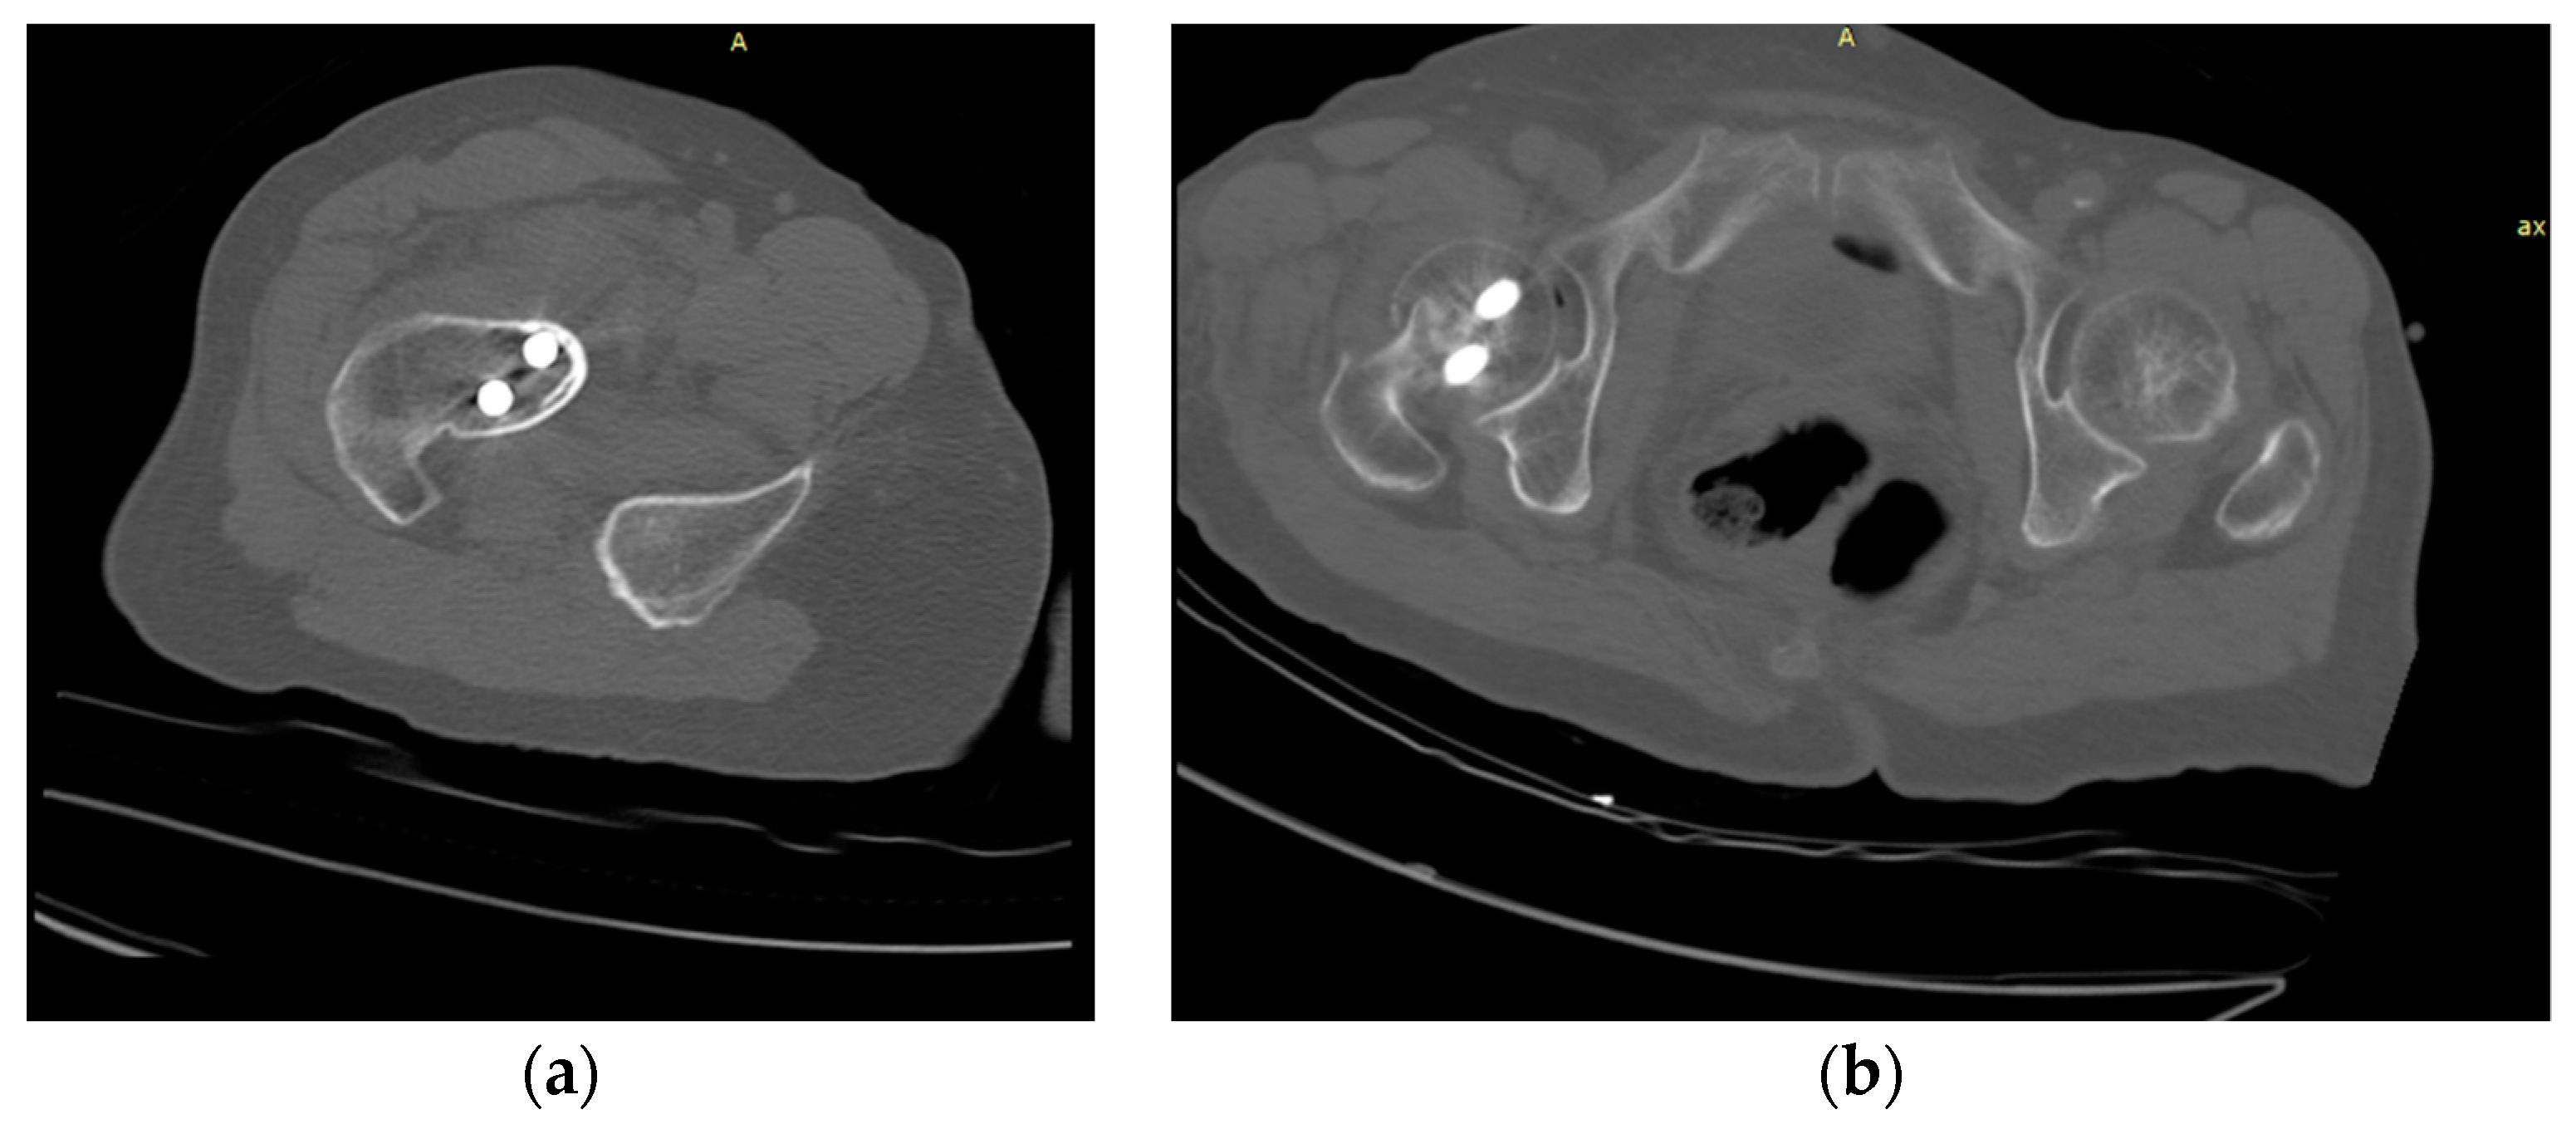

Figure 4 illustrates the different situations during a CT scan. Generally, in the examination during the recovery period from surgery, the CT data is cropped and transformed to provide a clearer and faster diagnosis, that is, a localized CT image of the left or right femur. In contrast, the complete femur and pelvis are sometimes retained in the CT image to visualize information around the fracture site. To obtain high robustness of the trained femur segmentation model and avoid the femur segmentation failure in the next step, we convert all images to the right, anterior, superior (RAS) anatomical coordinate system and use empty images to supplement the missing parts.

Figure 4.

The partial CT image versus the complete CT images: (a) partial CT images containing a single femur; (b) CT images containing the complete femur structure.